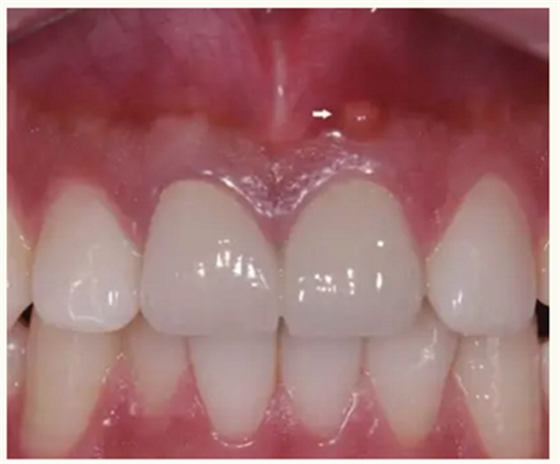

▲ 术前,21唇侧牙龈距离龈缘2mm处及瘘管

▲牙胶尖示踪显示瘘管与此相通

▲21牙根近中侧位于根尖1/3和根中1/3交界处有牙周膜间隙略增宽

▲术后,手术切口处疤痕

▲术后,X线显示:21根尖切除区域骨质修复,根管倒充填物完好,原牙周膜间隙增宽影消失